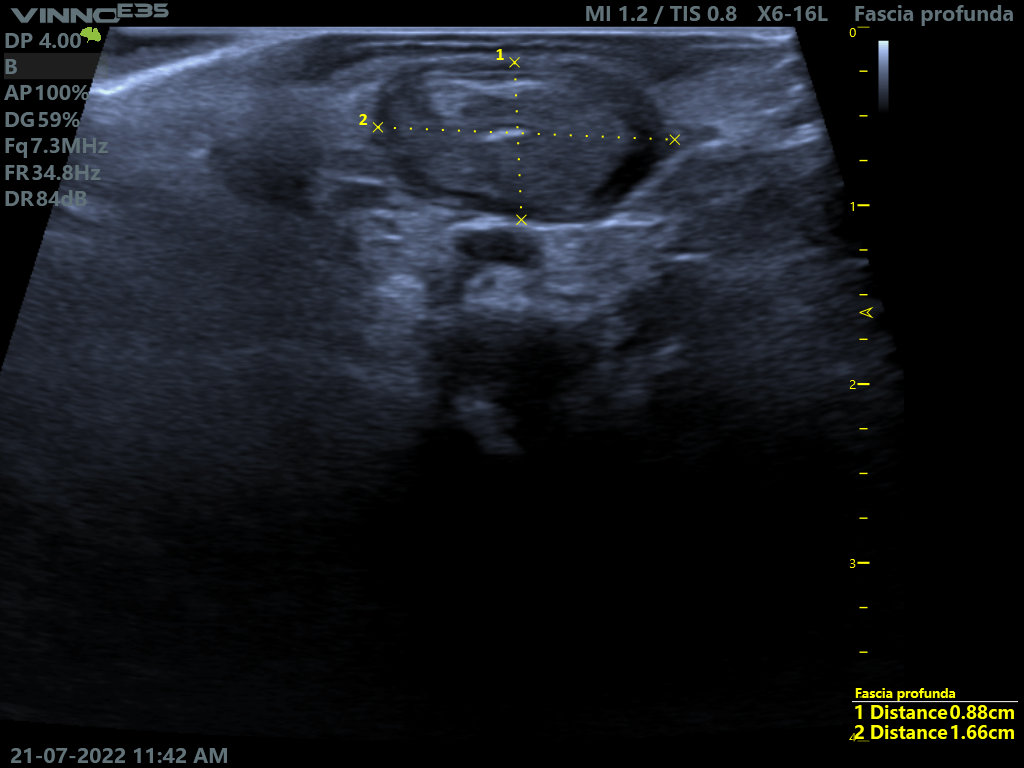

La infiltración ecoguiada es una técnica para tratar la patología articular, muscular, ligamentosa, del tendón y de la fascia mediante la introducción de sustancias medicamentosas con ayuda de un ecógrafo en tiempo real, con una precisión de practicamente en 100%, en el tejido o estructura lesionada. Gracias al uso del ecógrafo en las infiltraciones podemos acceder a la zona lesionada sin dañar otras estructuras durante el recorrido de la aguja y maximizar la acción farmaceutica, ya que el medicamento va solo a la zona dañada, lo que aumenta la probabilidad de éxito del tratamiento.

Por lo tanto, ayudará a aliviar el dolor, reducir la inflamación o mejorar la movilidad en enfermedades como artritis, tendinitis, fasciopatias o bursistis.

Casos prácticos